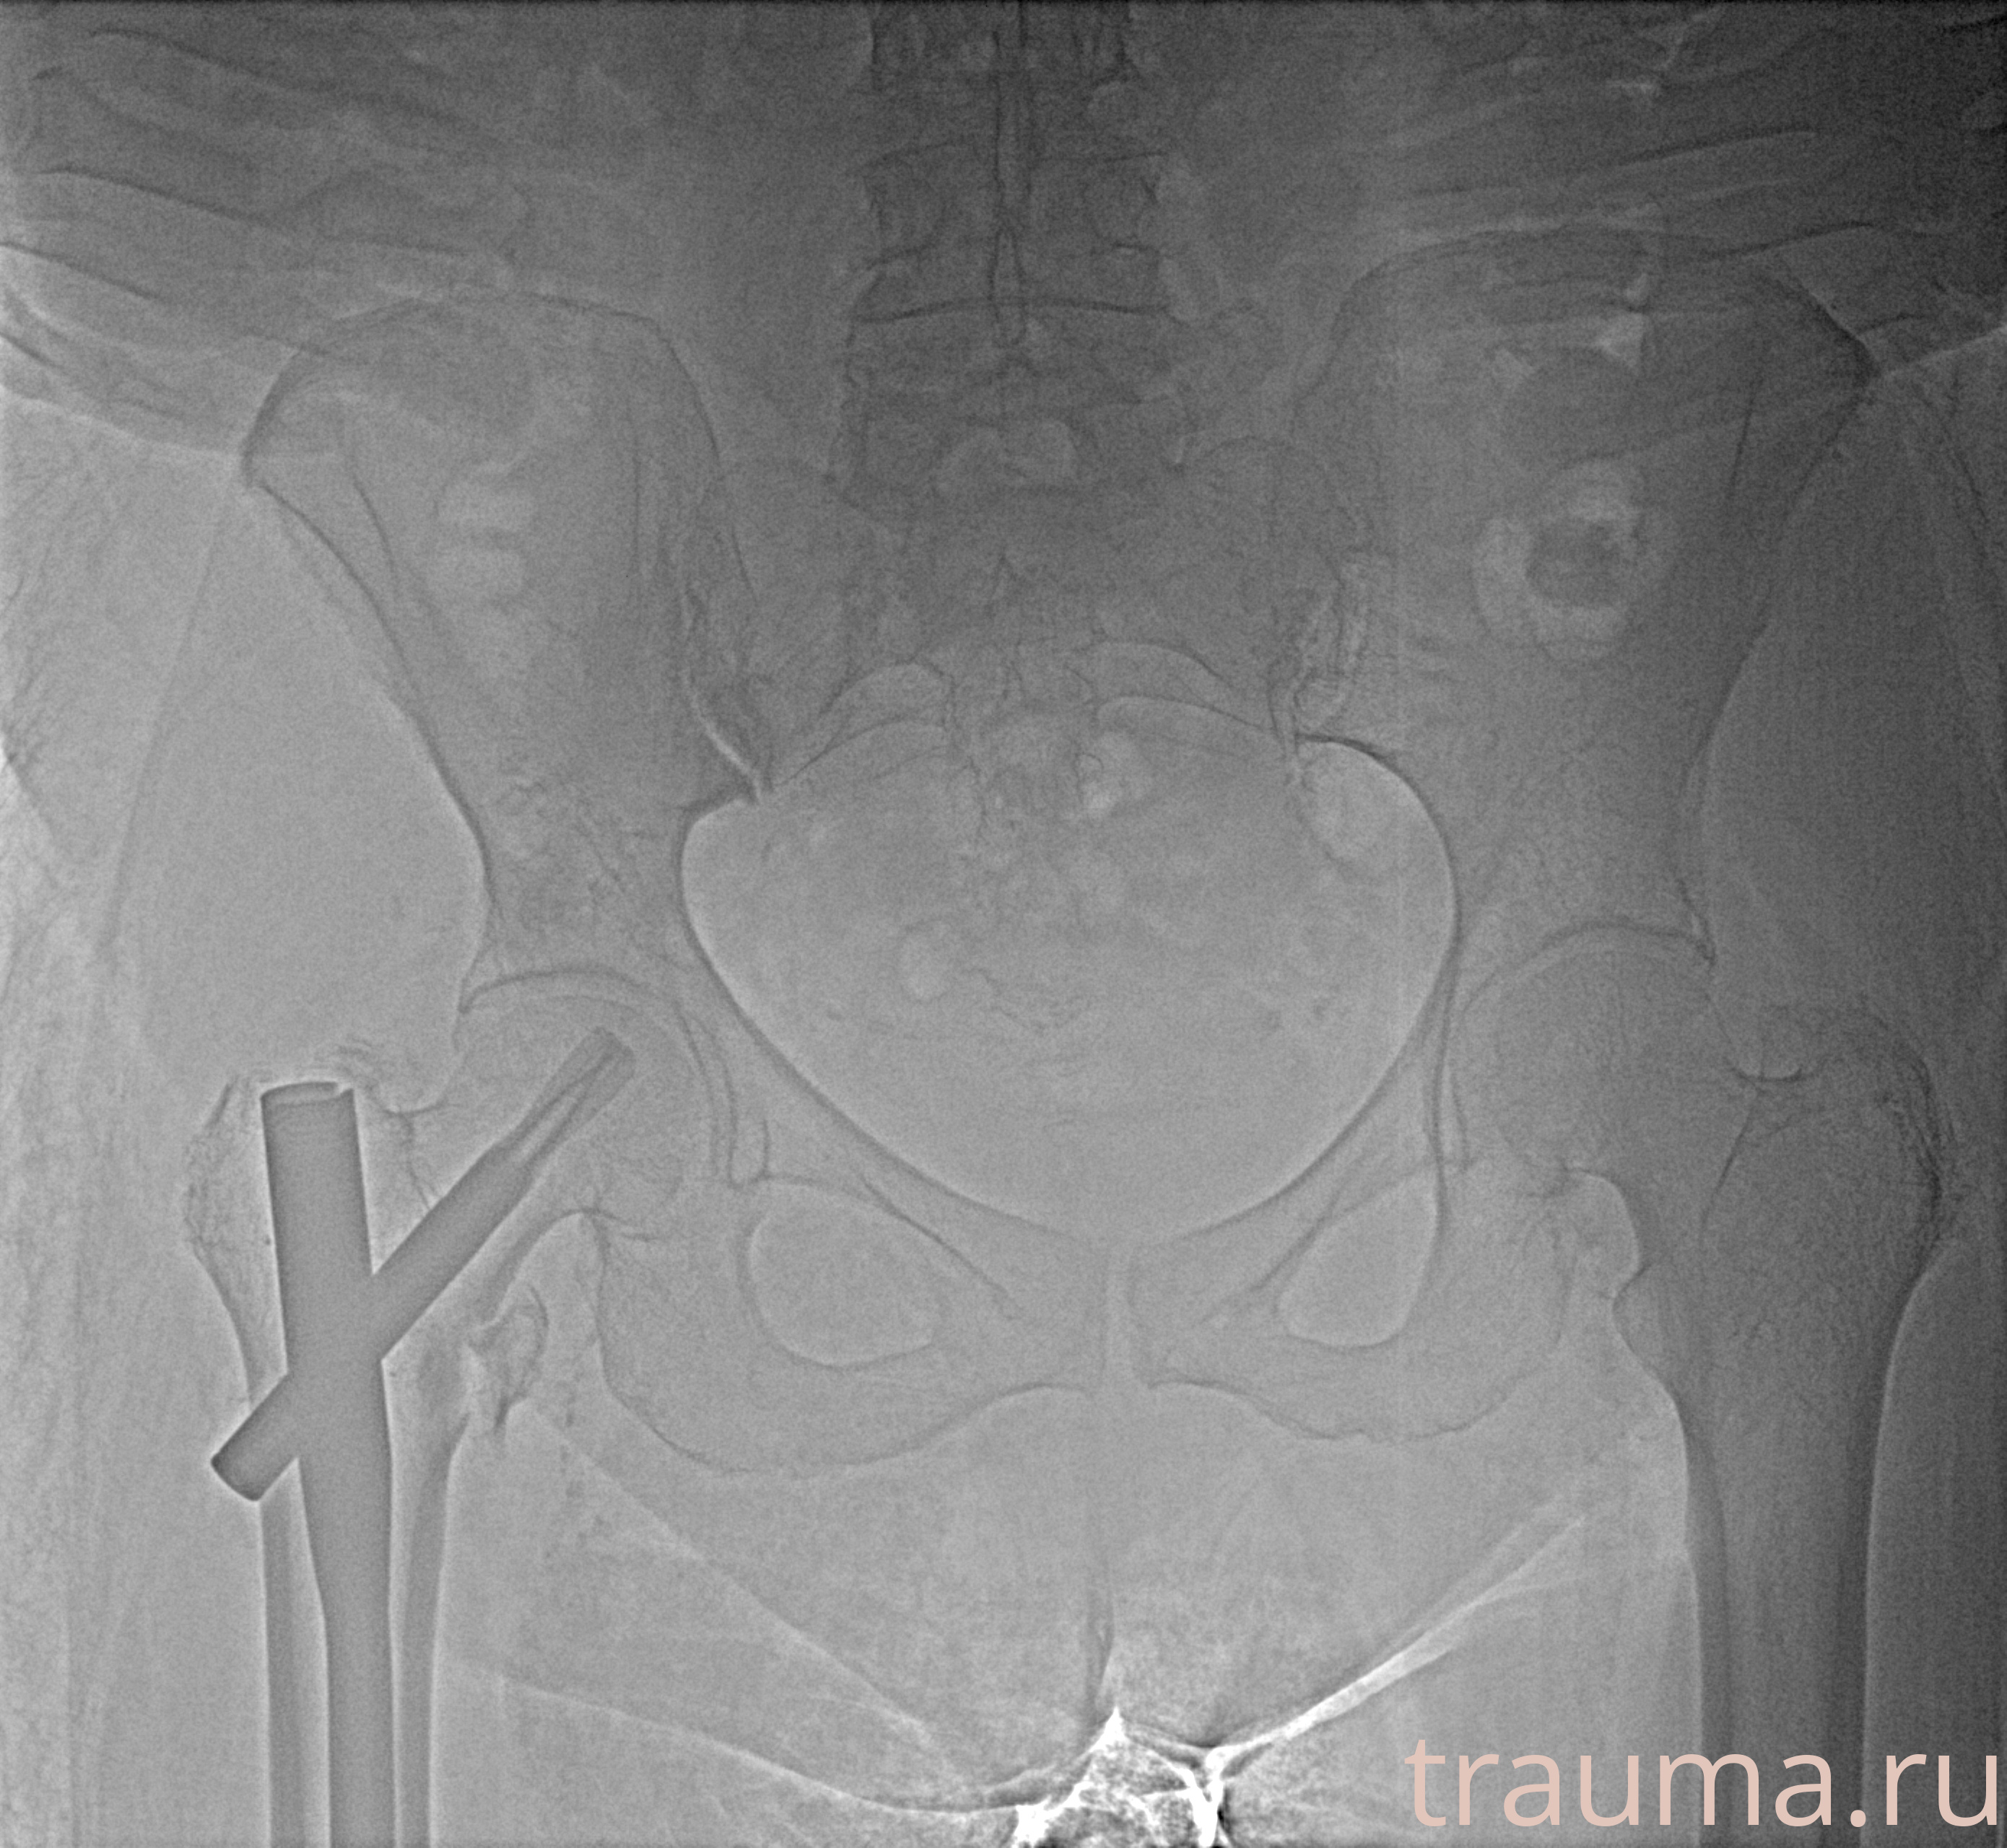

Рентгенограммы